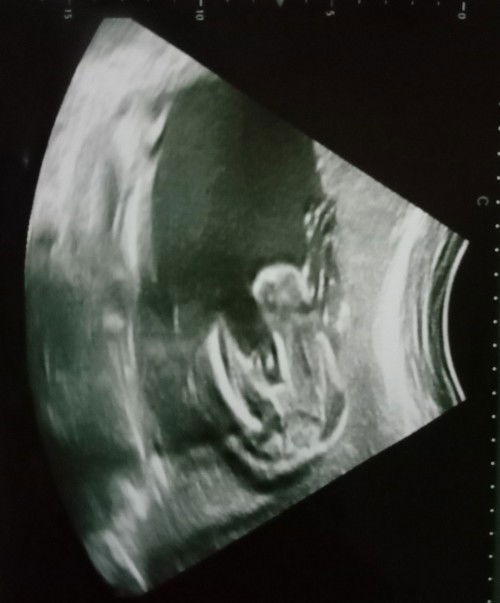

macam girl. saya rasa buat details scan lagi bagus sebab saya hampir 34 weeks baru dapat tahu gender dengan specialist.

mcm girl.. yg tgh2 tu mcm tali pusat.. wallahualam sy teka je berdasarkn gmbr ni hehe

girl klau x silap ni.. burger sign cuma tali pusat tu buat confius sikit..

mcm girl tp x pasti😍

Gegirl 🙈🙈

mcm girl

boy